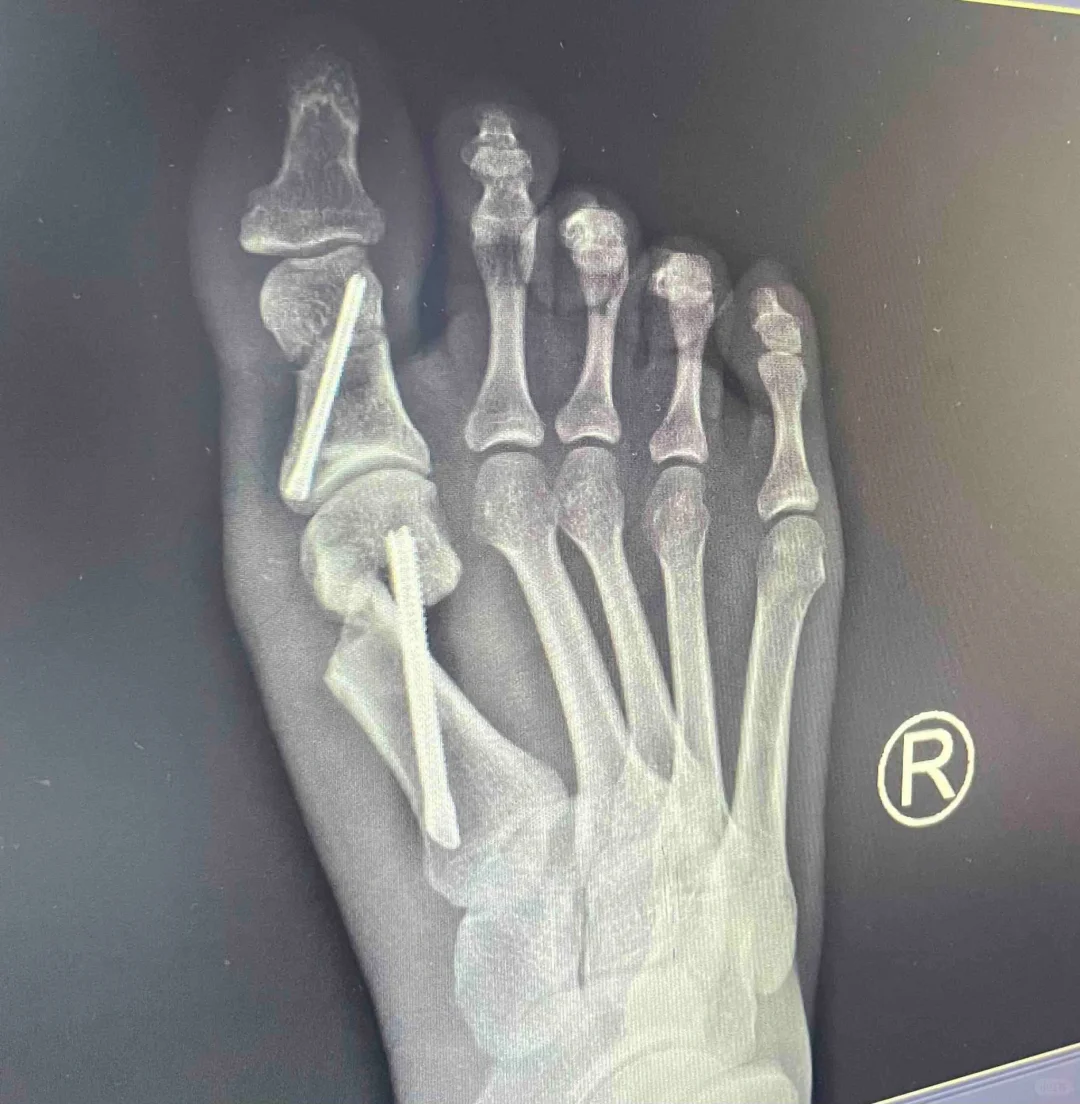

那么图四的片子能看懂了吗?